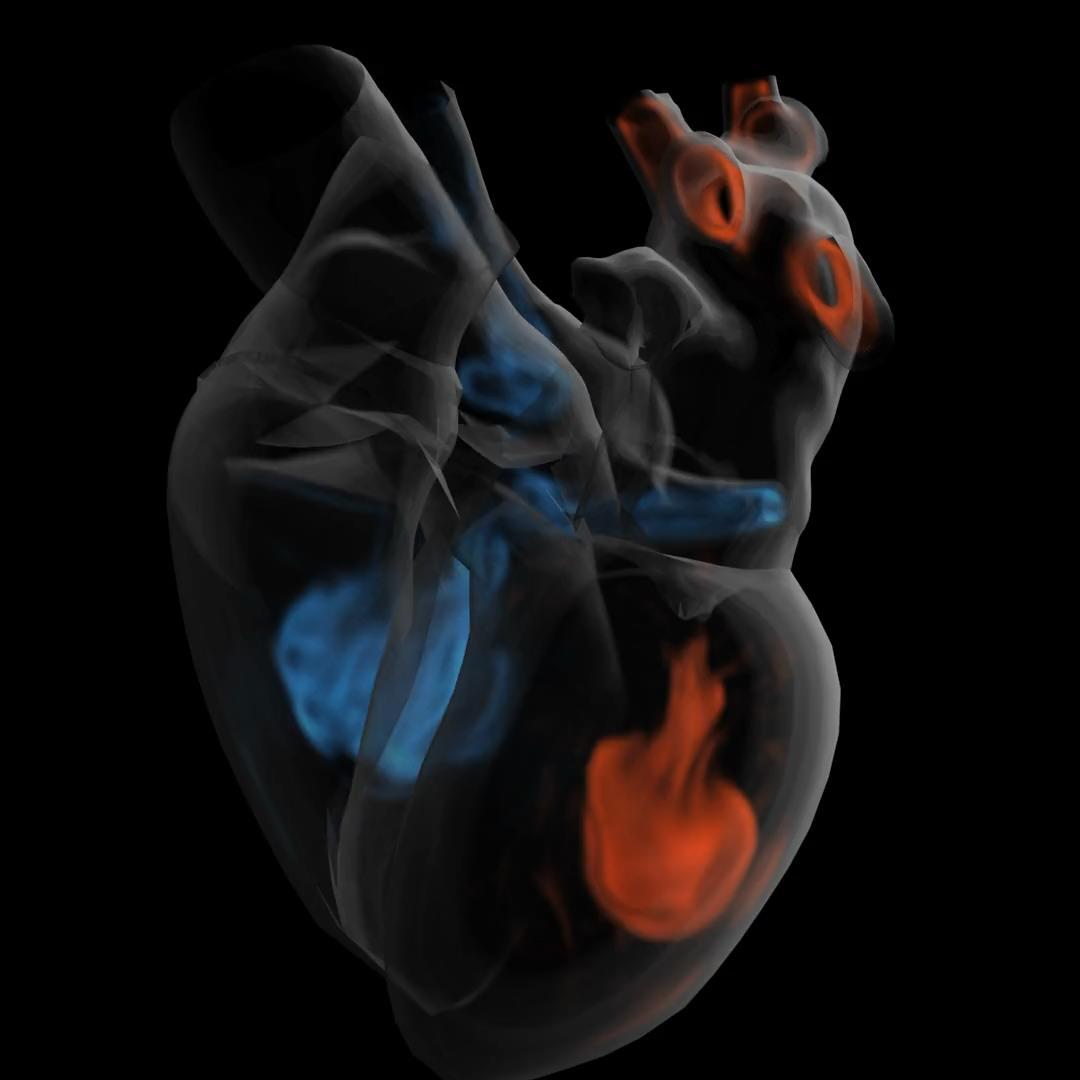

What if we could create a digital twin of the patient’s heart?

• Multiscale, Personalized Physiological Model of the patient’s heart

• Anatomy, Electrophysiology, Biomechanics (muscle contraction ), Circulation (ejection fraction, pressure dynamics)

• Mechanistic and statistical modeling

• Model is under our control

• Potential to test and prescribe best therapy for the patient – e.g., Cardiac Resynchronization Therapy

Ventricular Tachycardia Atrial Fibrillation Dyssynchrony – Heart Failure

Identify the ablation targets that will effectively terminate persistence AF? Identify the minimal ablation targets (catheter, RT) that will effectively terminate VT?

Cardiac radioablation –focus radiation using localization of VT exit

Anticipate the effects of CRT on patient’s cardiac function from preoperative data?